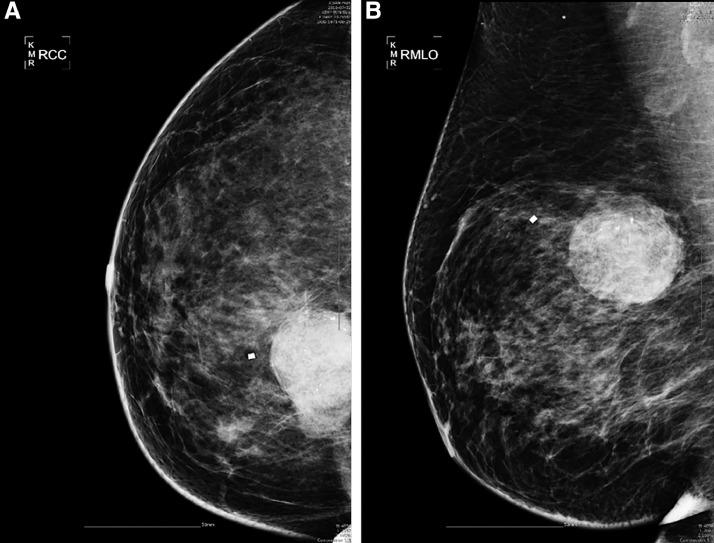

Malignant phyllodes tumor of the breast with liposarcomatous differentiation: A case report with imaging findings.

Phyllodes tumors are rare neoplasms that account for 2.5% of all fibroepithelial lesions, and 10%-20% exhibit malignant transformation. Malignant transformation often occurs in the form of stroma, and usually shows fibrosarcomatous differentiation. Liposarcomatous differentiation is a rare, developed stromal component of phyllodes tumors, and little is known about their imaging findings. We present the case of a 47-year-old woman who was diagnosed with a malignant phyllodes tumor of the breast that contained liposarcomatous elements. The patient underwent wide surgical excision of the mass and has been treated with adjuvant radiation therapy.

叶状肿瘤是罕见的肿瘤,占所有纤维上皮性病变的2.5%,其中10%-20%会发生恶变。恶变通常发生在间质中,且通常表现为纤维肉瘤样分化。脂肪肉瘤样分化是叶状肿瘤中一种罕见的、已发展的间质成分,关于其影像学表现知之甚少。我们报告一例47岁女性患者,她被诊断为乳腺恶性叶状肿瘤,其中含有脂肪肉瘤成分。该患者接受了肿块的广泛手术切除,并接受了辅助放疗。